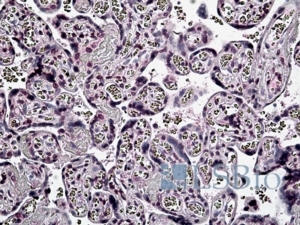

- Main image

- Experimental details

- EB06851 (3.8µg/ml) staining of paraffin embedded Human Placenta. Steamed antigen retrieval with citrate buffer pH 6, AP-staining.